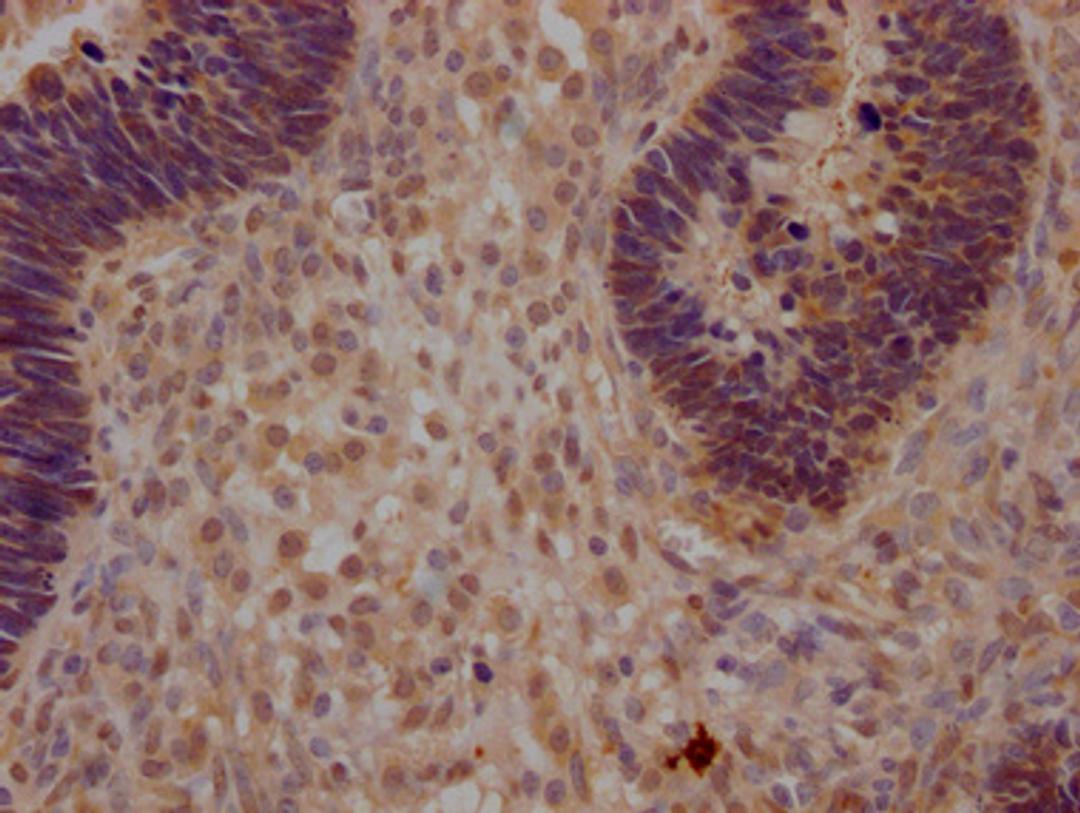

IHC image of CSB-PA026244LA01HU diluted at 1:200 and staining in paraffin-embedded human ovarian cancer performed on a Leica BondTM system. After dewaxing and hydration, antigen retrieval was mediated by high pressure in a citrate buffer (pH 6.0). Section was blocked with 10% normal goat serum 30min at RT. Then primary antibody (1% BSA) was incubated at 4°C overnight. The primary is detected by a Goat anti-rabbit polymer IgG labeled by HRP and visualized using 0.05% DAB.